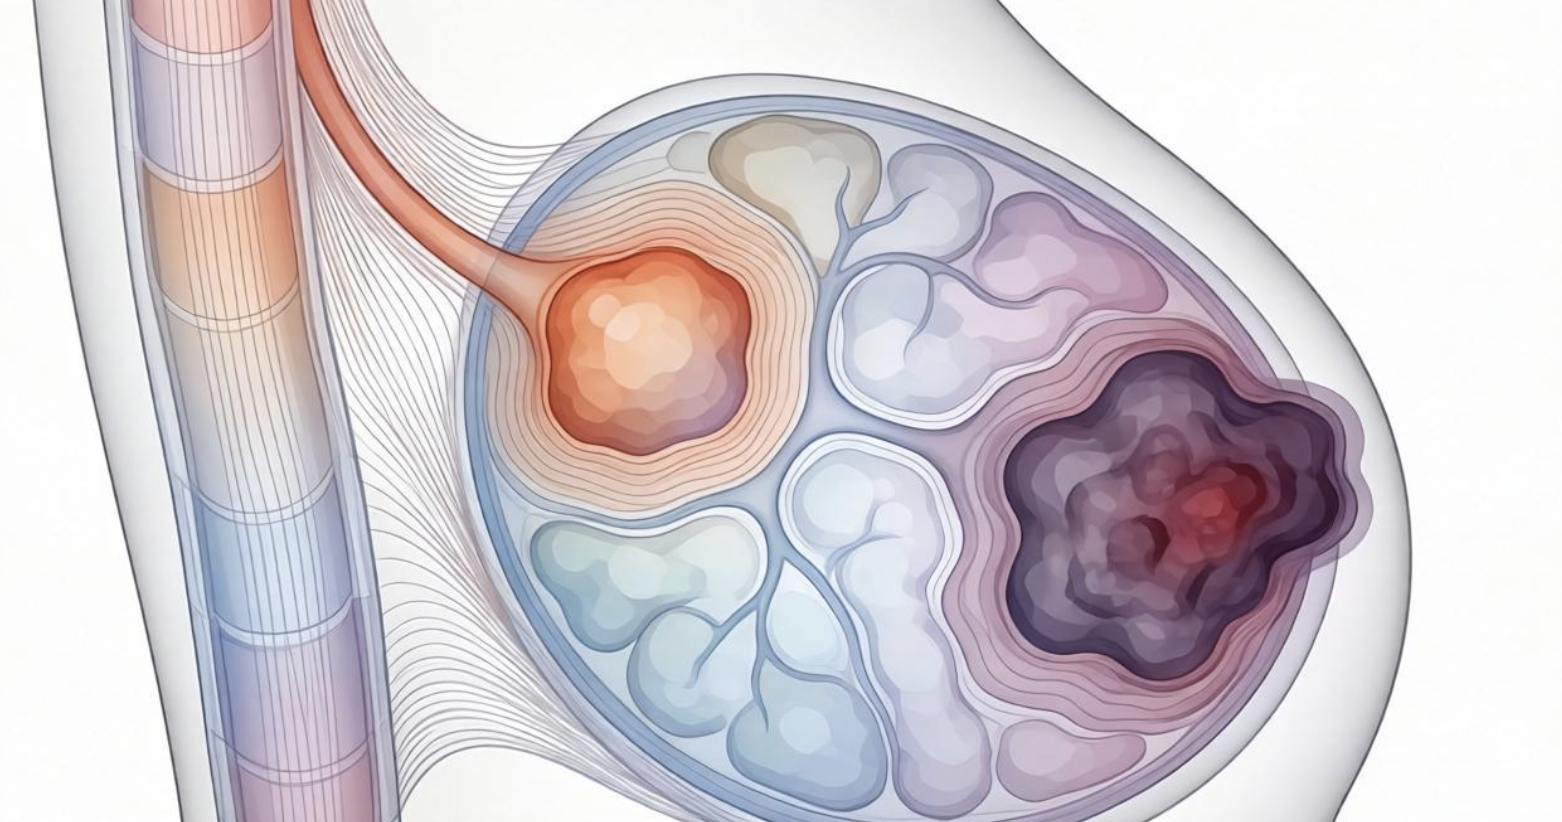

形态:规则与否,藏着风险信号

良性结节大多长得“规整”,多是圆形或椭圆形,轮廓圆润,就像光滑的小球,生长比较温和。而有恶性倾向的结节,形态往往不规则,可能是分叶状、有尖角,甚至像螃蟹脚一样呈浸润性生长,这种不规则形态,是风险升高的重要信号。

边缘:清晰或模糊,区分良恶很关键

边缘清晰、光滑锐利的结节,良性概率极高,说明结节和周围正常组织界限分明,没有侵袭性。而边缘模糊、毛糙,甚至出现毛刺状、星芒状改变的结节,就要高度警惕了,这种表现往往提示结节可能在向周围组织浸润生长,恶性风险会明显增加。

血流信号:血供多少,反映生长活跃度

结节的血流供应,能直接反映它的生长速度。良性结节生长缓慢,通常没有明显血流信号,或只有少量点状血流。而恶性结节生长速度快,需要大量营养支持,血流信号会很丰富,血管走形也会紊乱,出现穿支血管或血流团,这是判断风险的重要依据。

钙化:粗细形态,暗藏恶性线索

钙化是乳腺结节常见的表现,不同形态的钙化,良恶性差异很大。良性结节的钙化,多是粗大、分散的,比如大颗粒钙化,稳定性强,基本没有风险。而恶性倾向的钙化,常是细小、密集的泥沙样或分枝状钙化,聚集在一起,这种钙化是恶性病变的重要提示,需要重点关注。